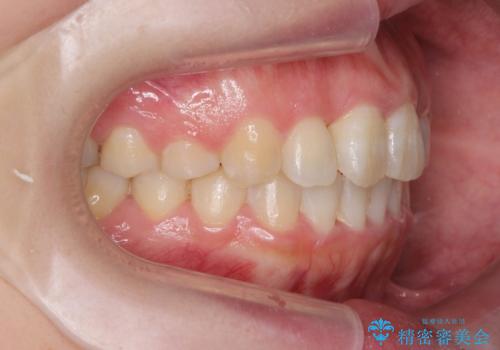

前歯のねじれをマウスピース矯正インビザラインで治療

- 長年気になっている、前歯のねじれの矯正治療を希望され来院されました。

十分にマウスピース矯正インビザラインで治療が可能と判断し、治療を進めることとしました。

長年気になっていた前歯のねじれが、ワイヤーをつけることなく矯正を行うことができ、大変喜んでいただくことができました。